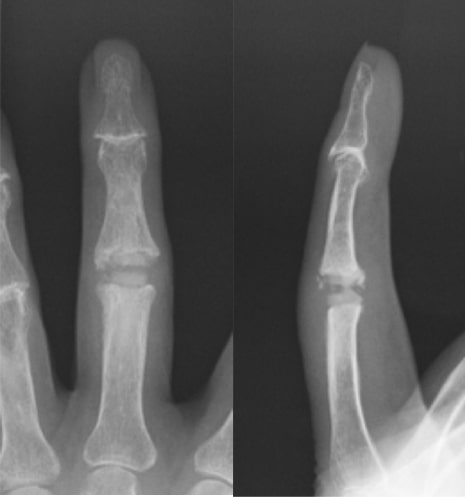

へバーデン結節

へバーデン結節写真

へバーデン結節術後写真

関節固定術後

原因

手指の第1関節(DIP関節)の変形性関節症であり、主に加齢性の変化と考えられます。

症状

DIP関節の痛みや腫れ、変形が進行します。特に水ぶくれのような腫瘤が生じることがあります(粘液嚢腫)。経過とともに、痛みは緩和することが多いですが、関節が動かしにくくなります。

治療方針

まずは、外用薬、テーピングなどの処方で様子をみます。痛みが強い場合には関節内注射をすることもあります。痛みが引かない場合や変形が目立って使い勝手が悪くなった場合は手術をします。手術は関節固定を行うことが多いです。

ブシャール結節

ブシャール結節写真1

ブシャール結節写真2

PIP関節の狭小化

ブシャール結節術後写真1

表面置換型人工指関節

ブシャール結節術後写真2

シリコン人工指関節

第2関節(PIP関節)の変形性関節症。関節リウマチなどの膠原病でも腫れてくることがあるので鑑別が必要です。

PIP関節がコブ状に膨らんで指が曲がって変形してきます。関節の痛みが強い場合も弱い場合もありますが、経過とともに、変形がすすみ関節が動かしにくくなります。どの指にも生じます。

まずは、外用薬、テーピングなどの処方で様子をみます。痛みが強い場合には関節内注射をすることもあります。痛みが引かない場合や動かなくなり使い勝手が悪くなった場合は手術をします。手術は人工指関節置換術を行う場合が多いです。人工指関節には色々な種類があります。